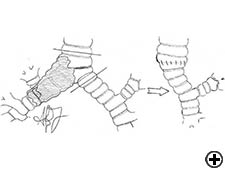

Carinal resection is a complex and aggressive procedure for the treatment of bronchial tumors involving the carina, the tracheo-bronchial angle or the distal portion of the trachea (Figure 1). The airway is reconstructed by anastomosis of the opposite main bronchus (tracheal sleeve pneumonectomy) or both bronchi (isolated carinal resection) to the lower trachea (Figure 2). The most common indication for a sleeve pneumonectomy is a tumor involving the origin of right main bronchus or extending into the lower trachea. Left sleeve pneumonectomy is rarely indicated since the left main bronchus is considerably longer than the right one and, in the case of carinal infiltration, tumor usually invades the structures in the subaortic space as well, which frequently implies inoperability. An isolated carinal resection and reconstruction may be applicable for centrally located, low grade and small tumors of the carina not extending so far to the main bronchi. Carinal resection represents a challenge for thoracic surgeons and anesthesiologists related to demanding intraoperative airway management, the technique of anatomic reconstruction and the risk of significant postoperative morbidity, mortality and poor long-term outcome [11].

In isolated carinal resection and reconstruction, applicable for centrally located, low grade and small tumors (Video 8), the right and left main bronchi can be medially sutured to create a new carina, that is subsequently anastomosed to the distal trachea (Figure 2C and Video 9). A less common technique provides the resection of the carina followed by an end-to-end anastomosis between the left main bronchus and the trachea, followed by anastomosis of the right main bronchus to the lateral, cartilaginous wall of the trachea, paying attention to stay at least 2 cm above the first anastomosis (Figure 6). When more advanced tracheal involvement is present, two alternative techniques may be used to avoid excessive tension: an end-to-end anastomosis between the right main bronchus and the trachea, followed by anastomosis of the left main bronchus to the lateral, cartilaginous wall of the bronchus intermedius or an end-to-end anastomosis between the left main bronchus and the trachea, followed by anastomosis of the right main bronchus to the lateral, cartilaginous wall of the left main bronchus (Figure 7). In all of cases a wide hilar release is mandatory to reduce tension on the anastomoses.